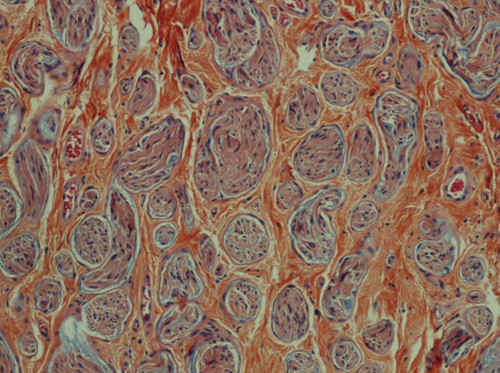

Ved kirurgisk eksplorasjon fant vi en hvitlig, relativt velavgrenset tumor som utgikk fra eller var adherent til en struktur vi oppfattet som restene av klitoris. Tumor var 1,5 cm stor og ble ekstirpert. Histologisk undersøkelse viste traumatisk nevrom (fig 1). Det postoperative forløpet var ukomplisert. Senere har kvinnen hatt en viss grad av vedvarende ømhet i området, men uten at det har vært mulig å påvise residiv av tumor ved palpasjon, ultralyd- eller MR-undersøkelse. Hun kan gjennomføre samleie uten smerte.